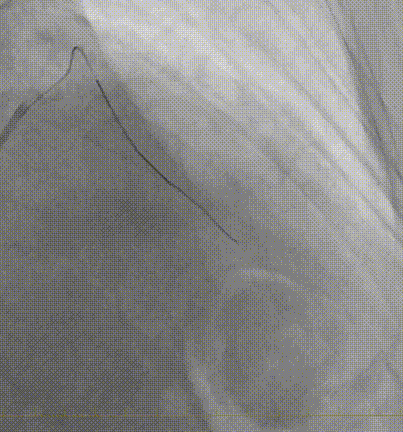

IVUS确诊夹层特征(图1F-G,视频3):

真腔受假腔压迫,假腔延伸至钙化斑块深部

LAD开口内膜撕裂,左主干未见明显夹层

图 1. 术中冠状动脉造影、IVUS及随访造影

F-G. IVUS:真腔受压,假腔延伸至钙化后方,内膜撕裂(黑色箭头)

J. IVUS:真腔扩大,多通道形成